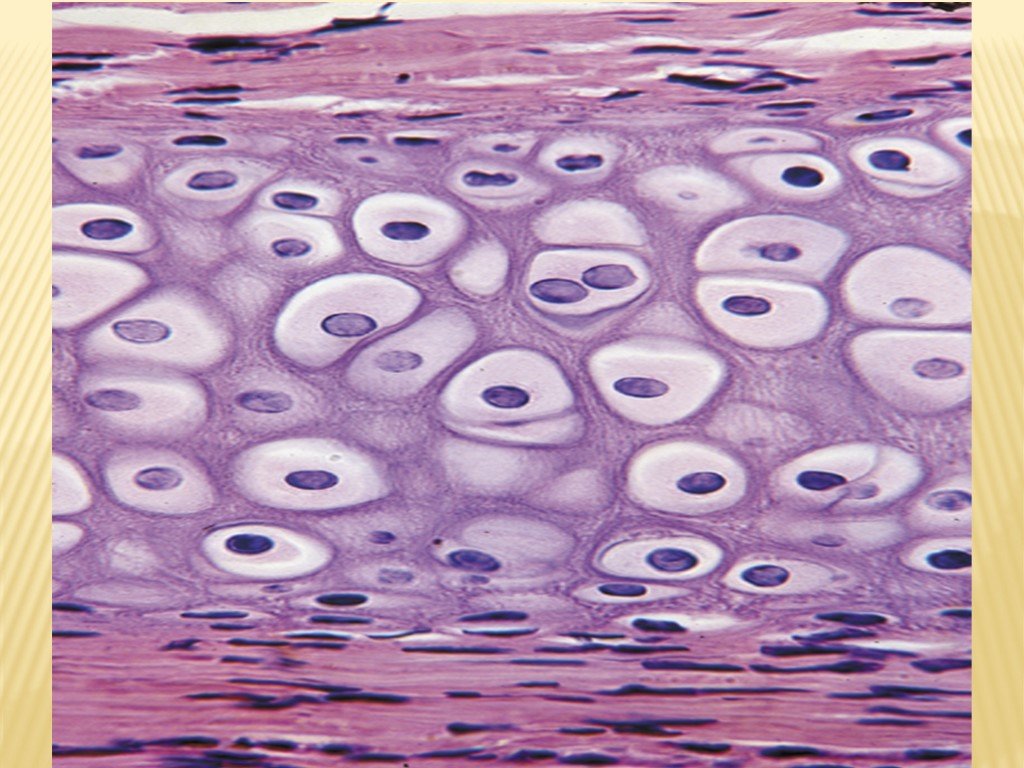

Структура грубоволокнистой костной ткани: наглядные примеры